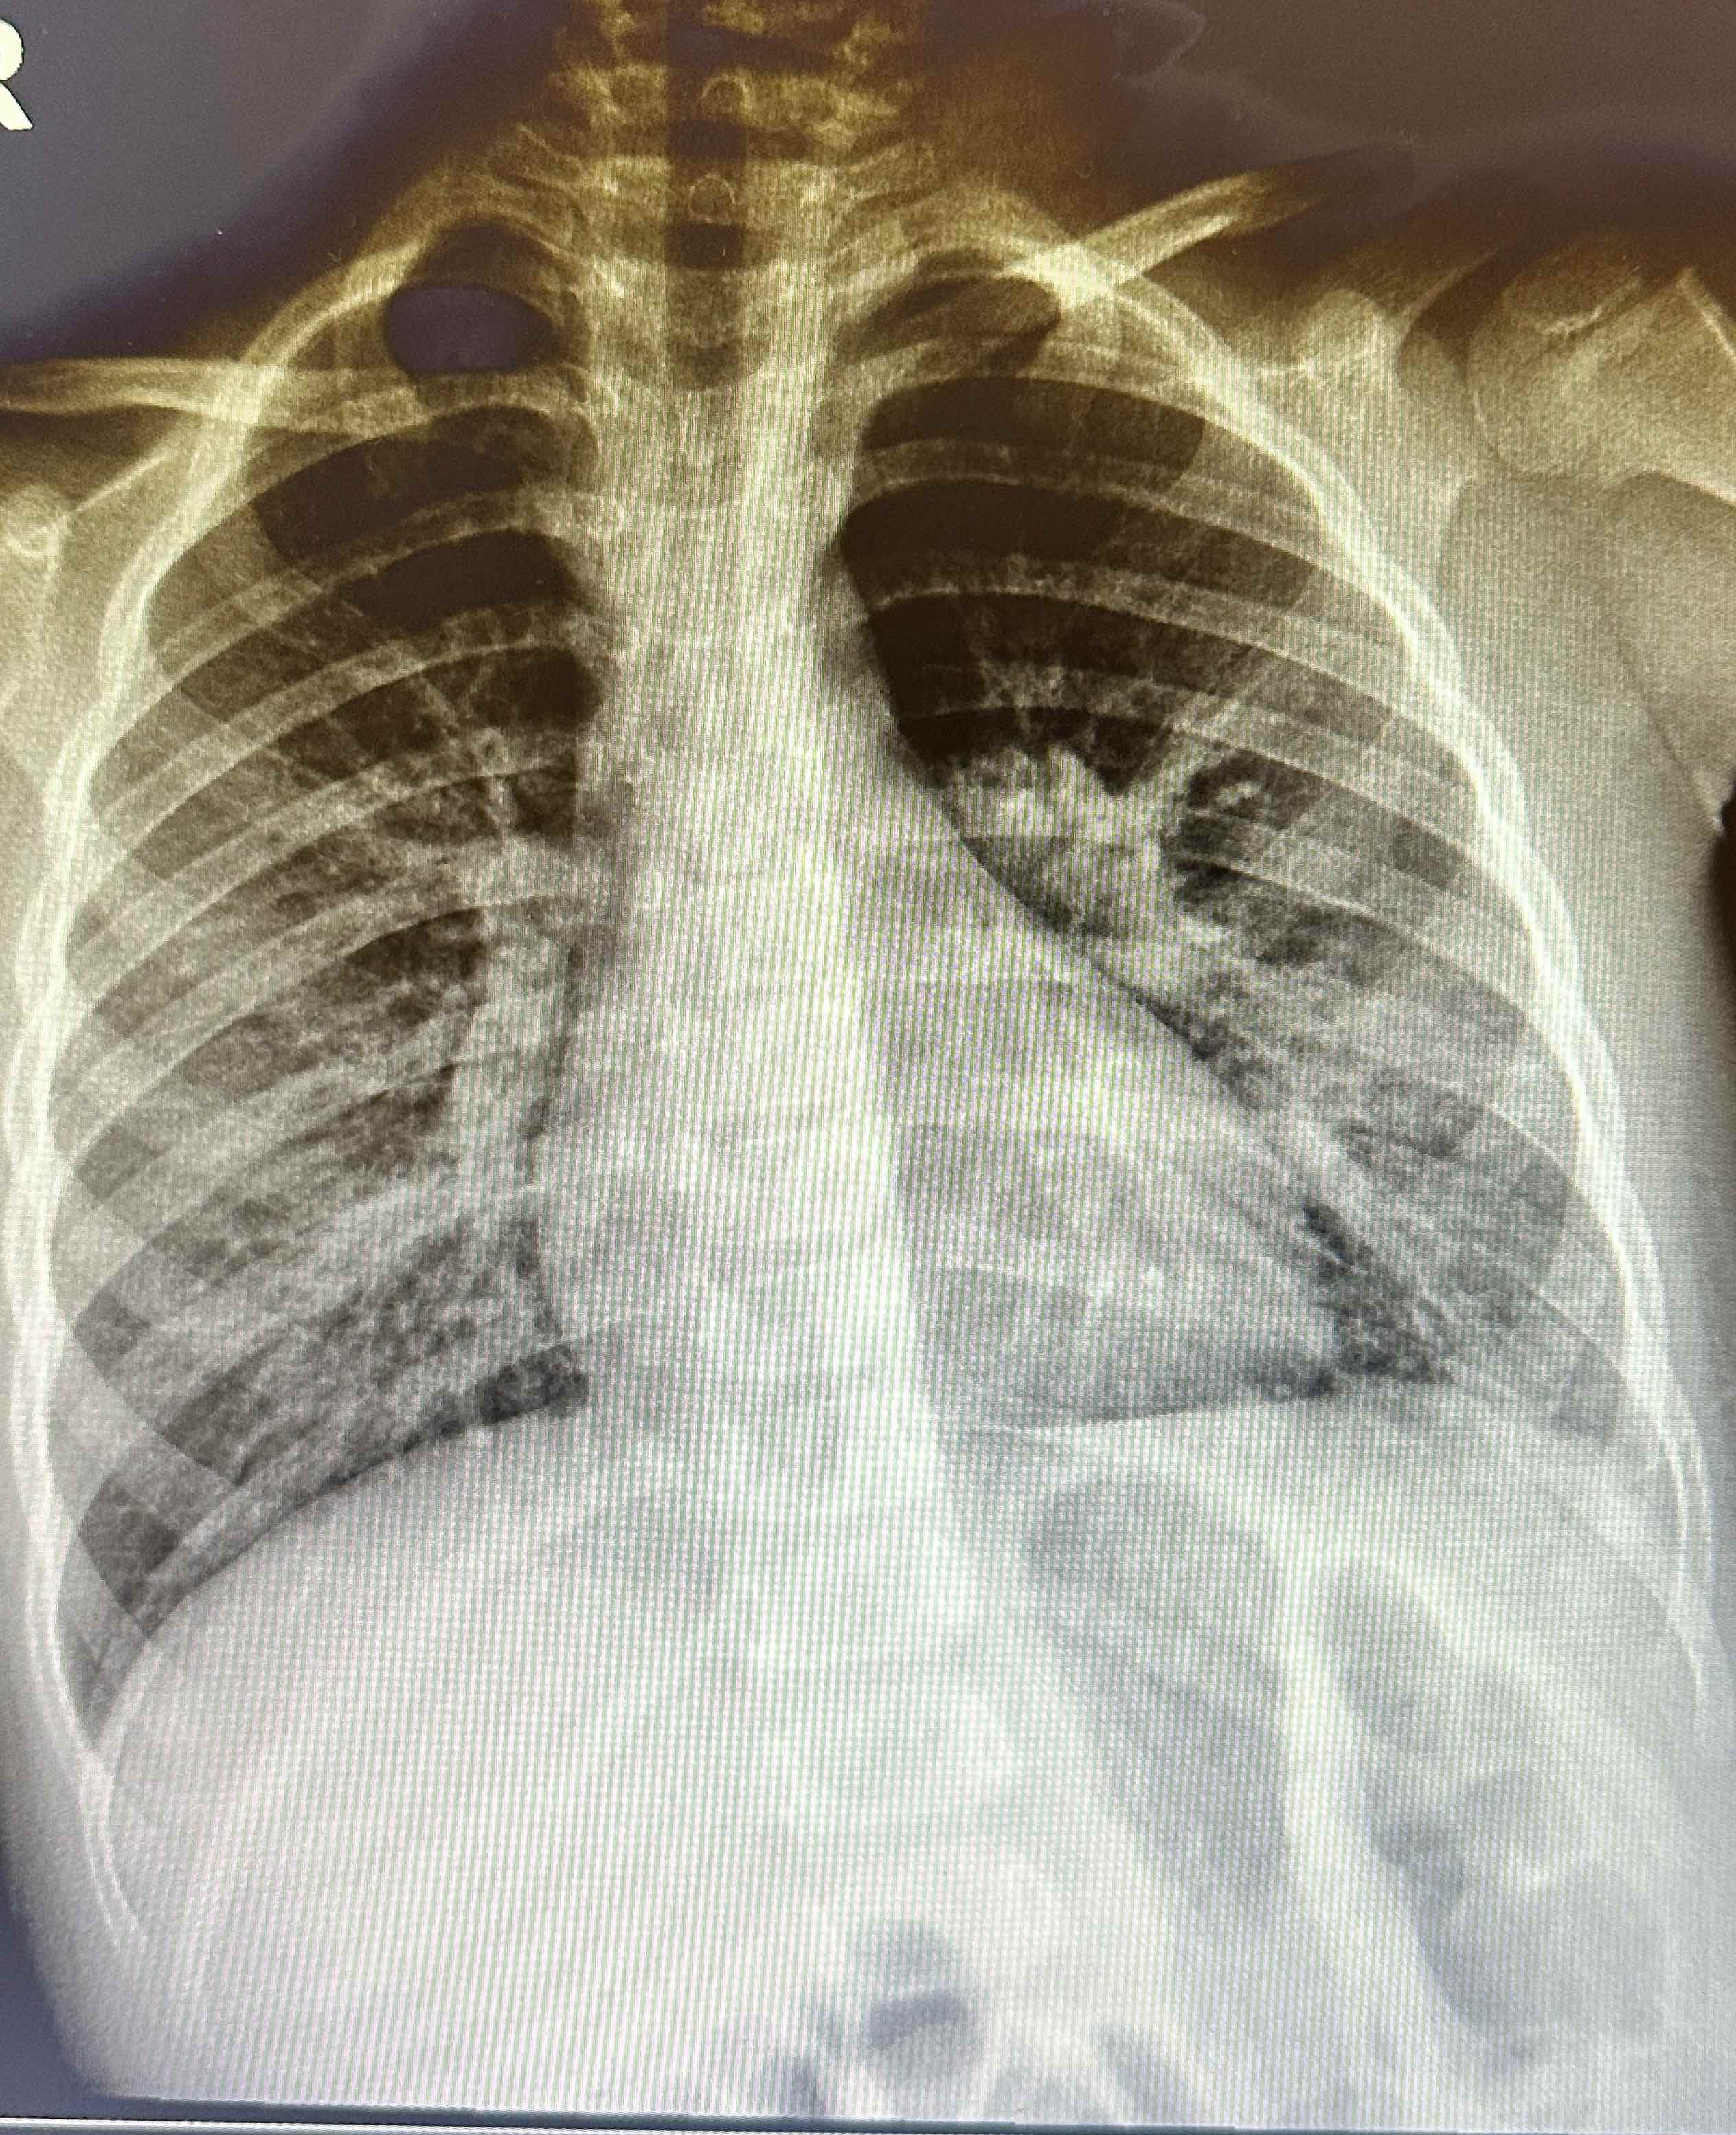

Lactante de 2 años sin antecedentes médicos o quirúrgicos conocidos, con esquema de vacunación completa, refieren los padres 3 días de presentar fiebre de hasta 39 ºC, continua y tos. Al Examen físico con buen estado general, llanto fácil pero consolable, activo y reactivo. Tórax: no tirajes costales, a la auscultación pulmonar con subcrepitante en base pulmonar izquierda e hipoventalación en zona lateroexterna basal izquierda. Se solicita radiografía de tórax en la que hay dudas sobre posible infiltrado basal por lo que se realiza ecografía pulmonar en la que se evidencian líneas B y pequeño derrame pleural.

La ecografía pulmonar es una herramienta valiosa para el diagnóstico de neumonía en niños, mostrando características específicas como consolidación, broncograma aéreo, líneas B y posibles derrames pleurales. Estos hallazgos nos ayudan a diferenciar entre diferentes tipos de neumonía, a evaluar la gravedad del estado del paciente y a resolver dudas radiológicas, sin embargo, lo ideal sería que al ser una prueba no invasiva y más cómoda para el paciente, esta se realizara en el Centro de Salud, evitando radiación innecesaria al paciente.